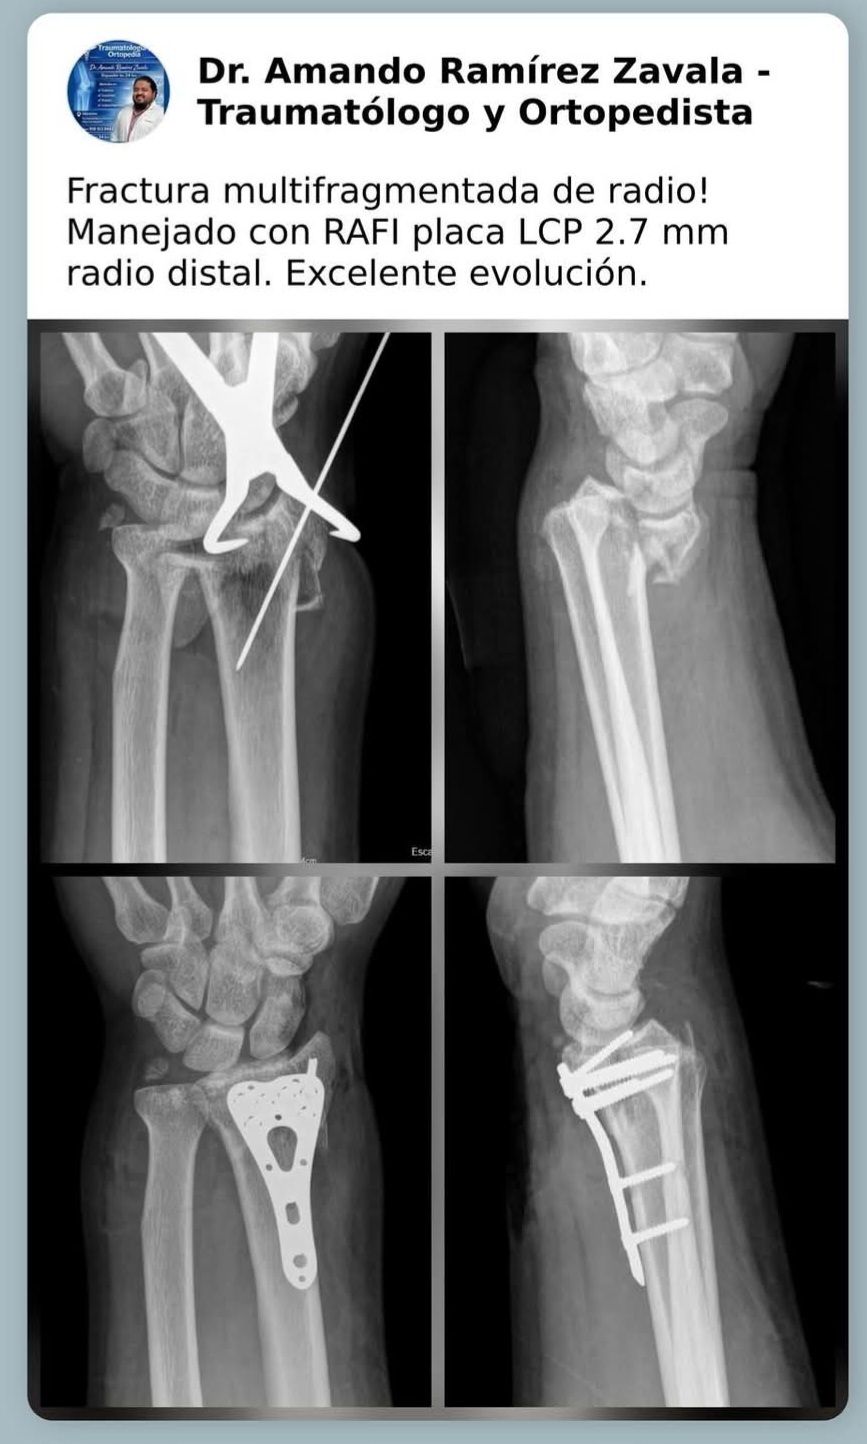

Mis habilidades más fuertes son el manejo de padecimientos de rodilla, cadera y hombro, así como procedimientos quirúrgicos asociadas a enfermedades degenerativas, fracturas y luxaciones.